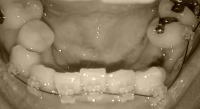

以下、画像です。

beforeU.jpg 5月?日(抜歯前)

060905b.jpg 6月20日

061129b.jpg 今日